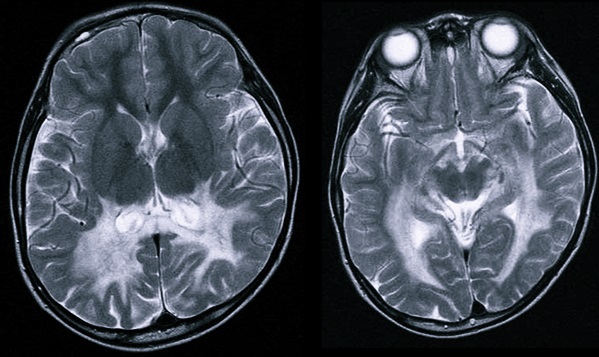

МКБ-10 классифицирует несколько видов поражения мозга, которые врачам важно дифференцировать от ПВЛ: церебральная лейкомаляция, глиоз, поликистозная энцефаломаляция, субкортикальная лейкомаляция. Их симптомы схожи, разницу клинической картины показывает своевременно сделанная МРТ.

МРТ детям делают под наркозом, потому что они не в состоянии без движения вылежать необходимое время обследования.